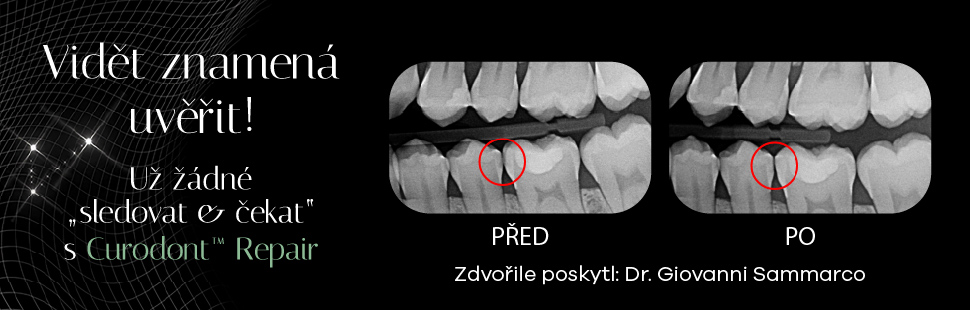

Autoři článku diskutují o významu remineralizace a demineralizace v procesu vzniku zubního kazu.

Zubní kaz je celosvětově nejrozšířenějším neinfekčním onemocněním. Jedním z důvodů je skutečnost, že jeho počáteční stadia, která lze považovat za subklinické projevy kariézního procesu, jsou často řešena přístupem „sledovat a čekat“. Tento přístup však nese riziko progrese kazu³ a v závažných případech může vést i k vážným zdravotním komplikacím.